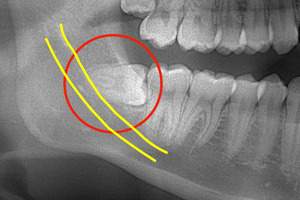

1回目から3ヶ月経ってからCTを撮影したものです。下歯槽神経の位置が根の先端から離れているのが確認できます。これで下歯槽神経を損傷させることなく、親知らずの抜歯を行うことができます。

麻布十番歯科の親知らずの1回目の治療から3ヶ月経過した状態を確認するためのCT画像